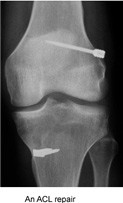

Orthopedic Surgery

Sports Medicine

An ACL repair